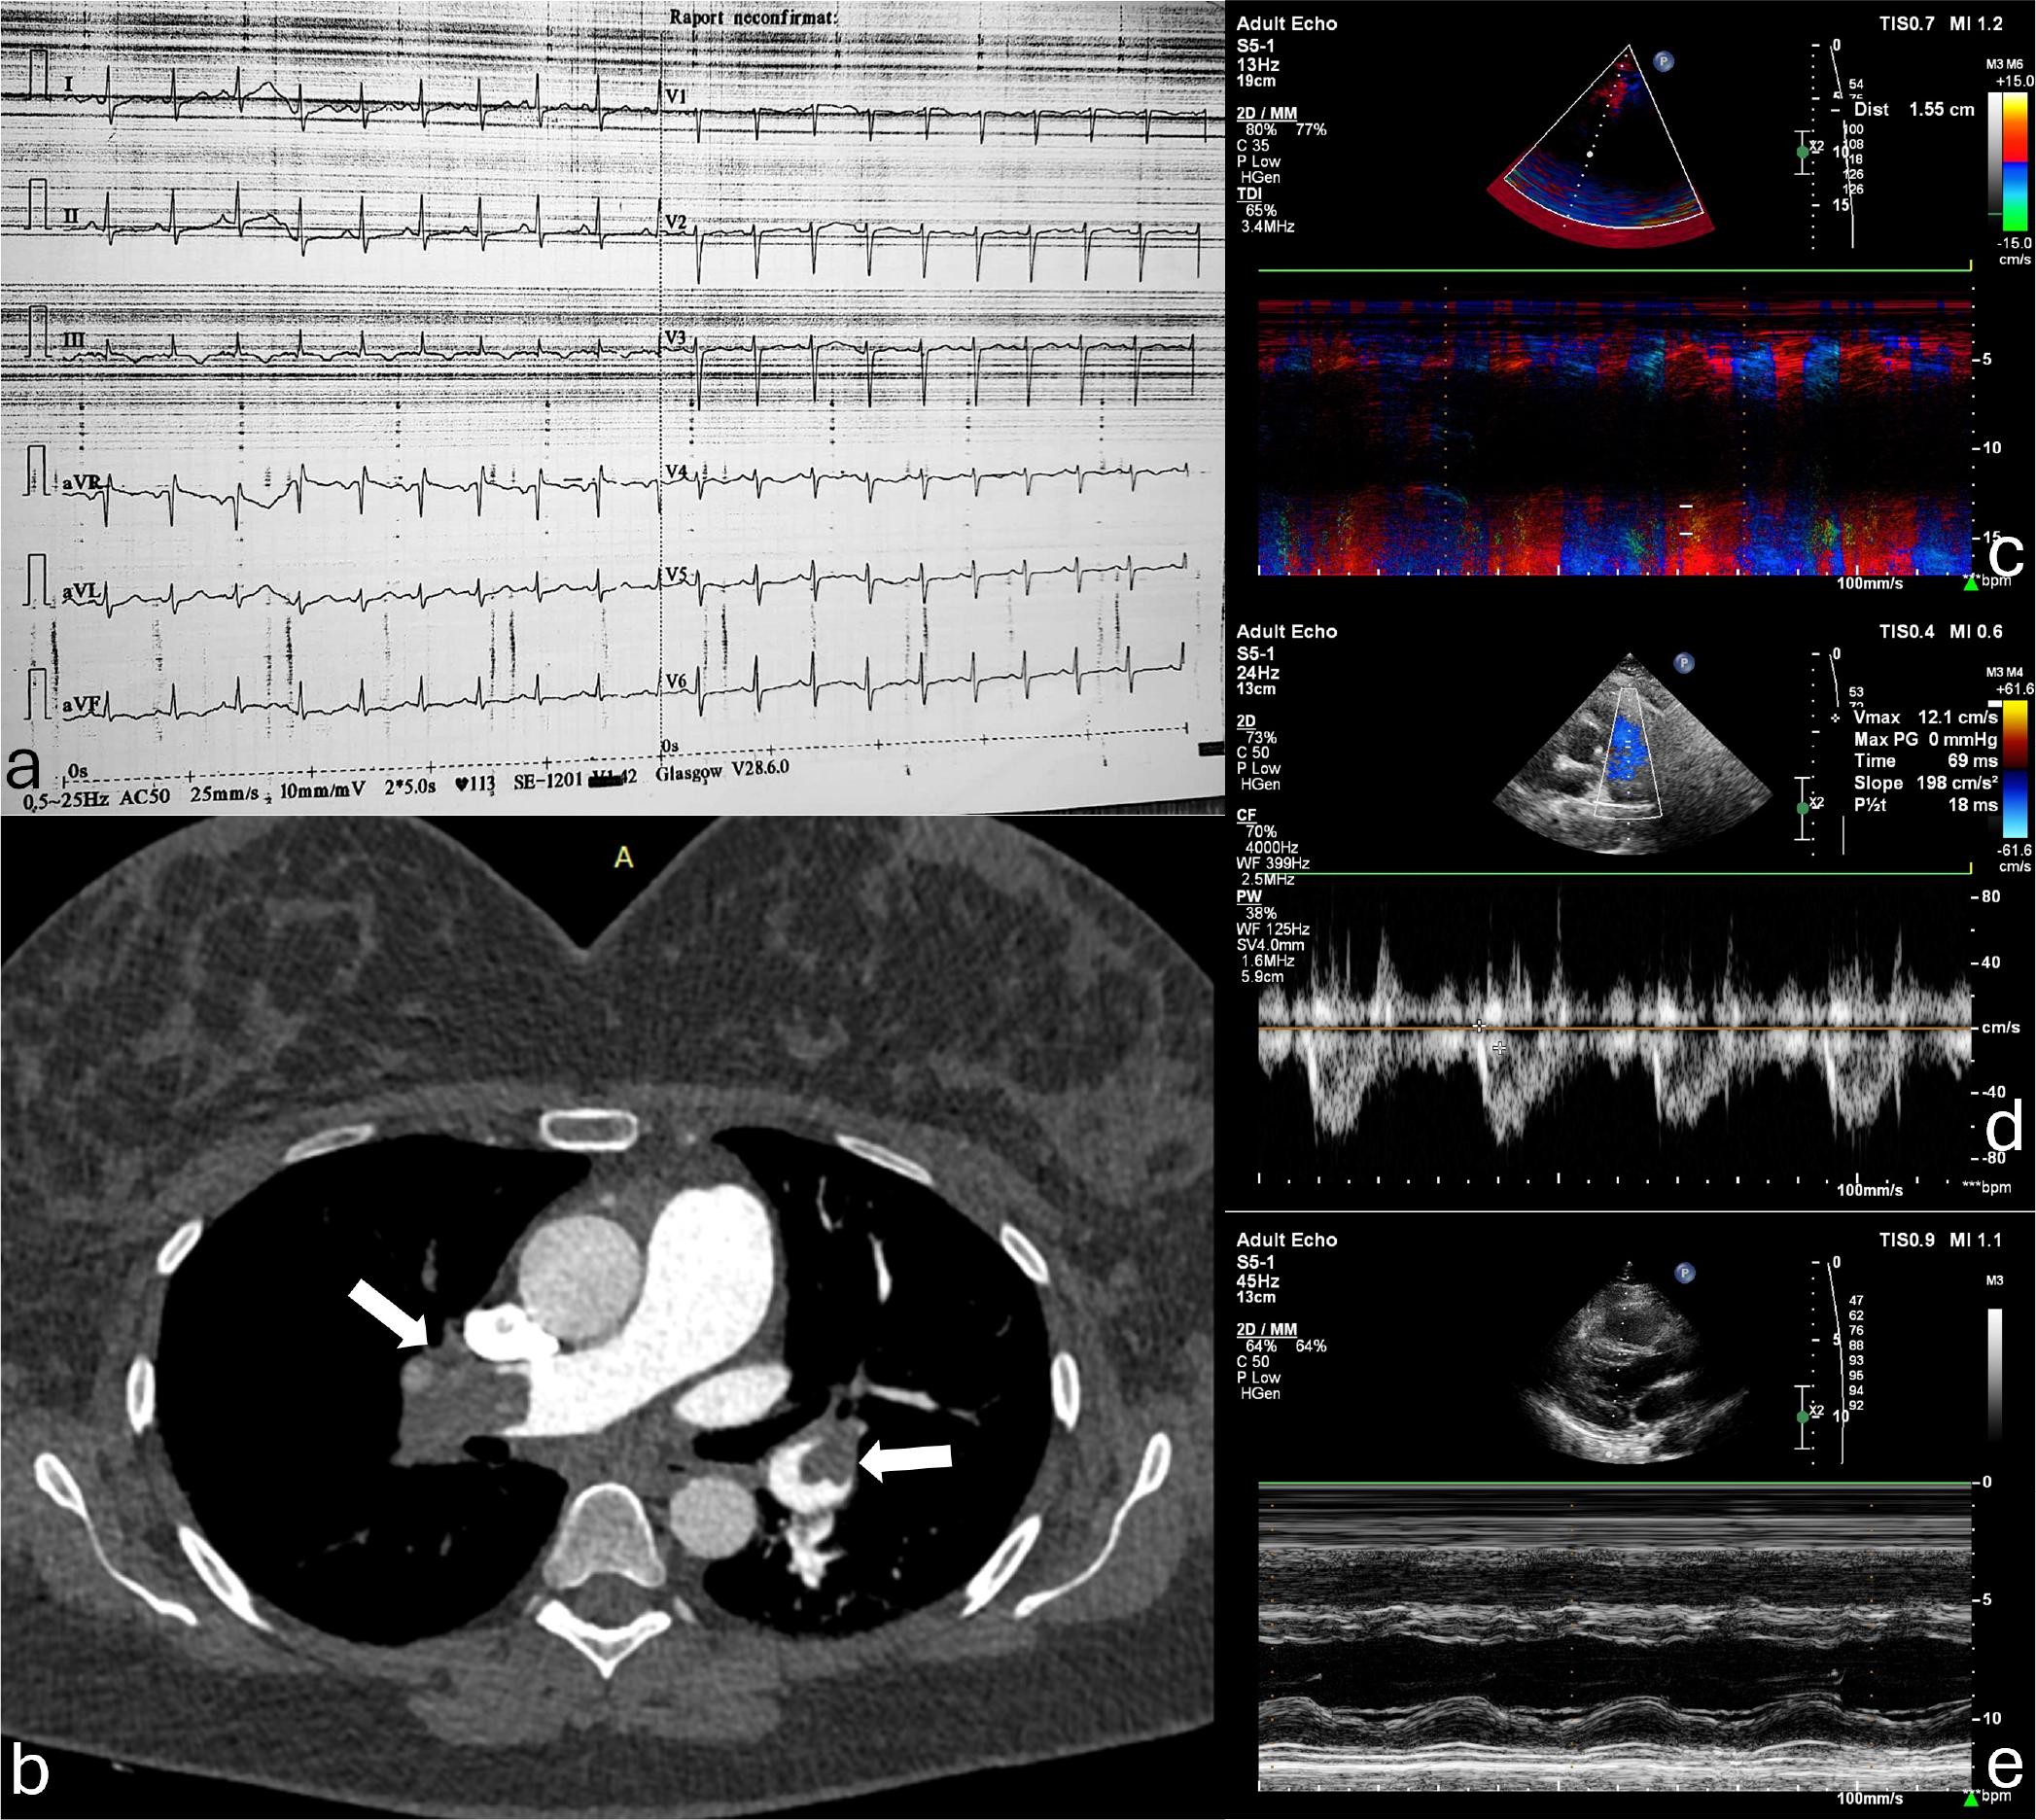

The electrocardiogram showed sinus tachycardia of 113 bpm and signs of right ventricular strain (negative T waves in the inferior leads and T wave abnormalities in the anterior leads) as well as the McGinn-White pattern – S1Q3T3 (Figure 1). Laboratory tests performed in the emergency department showed mildly increased highly sensitive I troponin levels (75.9 ng/L; normal range under 29 ng/L), and increased NT-proBNP levels (2248 pg/mL; normal range under 125 pg/mL).

Diagnostic tests before treatment decision. a. Electrocardiogram in the Emergency Department (V-25mm/sec, A-10mm/mV) depicting sinus tachycardia, right ventricular strain, and S1Q3T3 (McGinn-White) pattern. b. Computed tomography pulmonary angiography showing the obstruction of the pulmonary arteries (arrows). c-e. Echocardiographic images registered in the Cardiology Ward, showing a reduced (15.5 mm) tricuspid annular plane systolic excursion (TAPSE) measured by M-mode (c), a severely reduced pulmonary artery acceleration time (69 msec), with a mid-systolic notch (d), and the flattening of the interventricular septum due to the increased right ventricular pressure (e).

Echocardiography revealed a dilated right ventricle with a decreased systolic function (tricuspid annular plane systolic excursion of 15mm), a moderate tricuspid regurgitation, with a transvalvular gradient of 50 mmHg, a dilated inferior vena cava with no inspiratory collapse. An additional sign of increased pressure in the right chambers was the paradoxical septal motion of the interventricular septum and a D-shaped left ventricle (Figure 1).

Based on these findings, noted in the presence of postpartum status (moderate risk factor), and the results of predictive scores for the likelihood of PE (moderate risk group in the Geneva- and Wells scores, and 2 positive criteria of the PERC rule), a computed tomographic pulmonary angiography was performed. The investigation showed acute obstruction of both pulmonary arteries, extending bilaterally to all lobar branches (Figure 1). The patient was admitted to the Cardiology Ward for further investigations and antithrombotic treatment. A gynecology consultation was also performed in the emergency department, which excluded any active hemorrhagic sources as well as any local complications of pregnancy and childbirth as a potential contraindication for systemic thrombolysis.